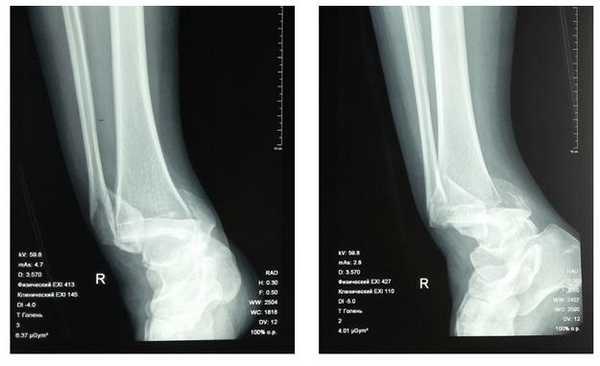

Пациентка Л. 50 лет, травма в быту, получила закрытый перелом обеих лодыжек с вывихом стопы кнаружи и кзади. Данный случай интересен значительным повреждением мягких тканей произошедшем при травме и потребовавшем значительных усилий в борьбе с отёком, а также морфологией перелома внутренней лодыжки, сломавшейся одним большим блоком вместе с задним краев большеберцовой кости, что потребовало её фиксации при помощи пластины и винтов.

В связи с выраженным отёком мягких тканей, высоким риском некроза краёв ран и инфекционных осложнений пациентке с целью предоперационной подготовки выполнялись скелетное вытяжение, сосудистая и метаболическая терапия, лимфодренаж, физиотерапия. После спадения отёка, на 3 день после поступления выполнено оперативное вмешательство: открытая репозиция, остеосинтез переломов наружной и внутренней лодыжек пластинами и винтами.

Через 4 дня пациентка выписана на амбулаторное долечивание. Послеоперационные раны зажили первичным натяжением, швы удалены через 14 дней.

Через 6 недель после первичного вмешательства произведено удаление позиционного винта, пациентка приступила к активной разработке движений в голеностопном суставе.

Амплитуда движений через 8 недель после травмы и оперативного вмешательства по поводу этого тяжёлого повреждения близка к полной. Пациентка ходит с полной опорой, не используя костыли или трость, не хромает, боли не беспокоят. Сохраняется умеренный отёк в области голеностопного сустава.